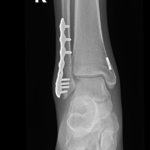

if the fracture is displaced, surgery may be needed to put the bone back into the correct position and fix the bone with Plates & screws or nails for adequate healing to occur.

- Ankle Fractures.